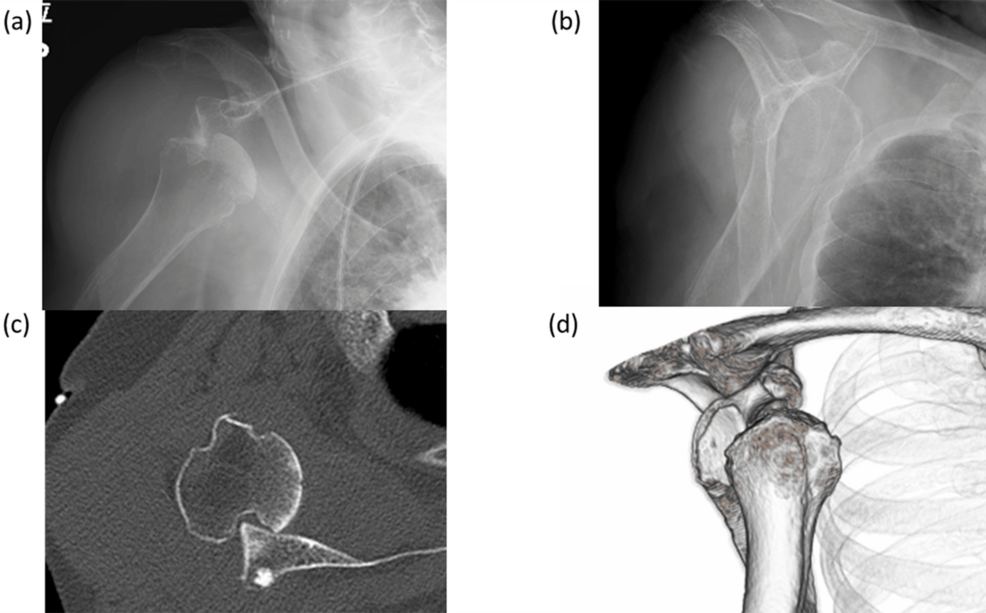

Un caso clínico publicado por Cureus detalla el tratamiento exitoso de una lesión compleja en el hombro utilizando artroplastia inversa. El paciente presentaba un quiste de gran tamaño con cuerpos libres intraarticulares (conocidos como «cuerpos de arroz»), un desgarro irreparable del manguito rotador y una lesión de Hill-Sachs.

La lesión de Hill-Sachs, una depresión en la cabeza humeral, a menudo acompaña a las luxaciones de hombro. En este caso, la combinación de la lesión de Hill-Sachs, el desgarro del manguito rotador y el quiste intraarticular presentaba un desafío significativo para la reparación convencional.